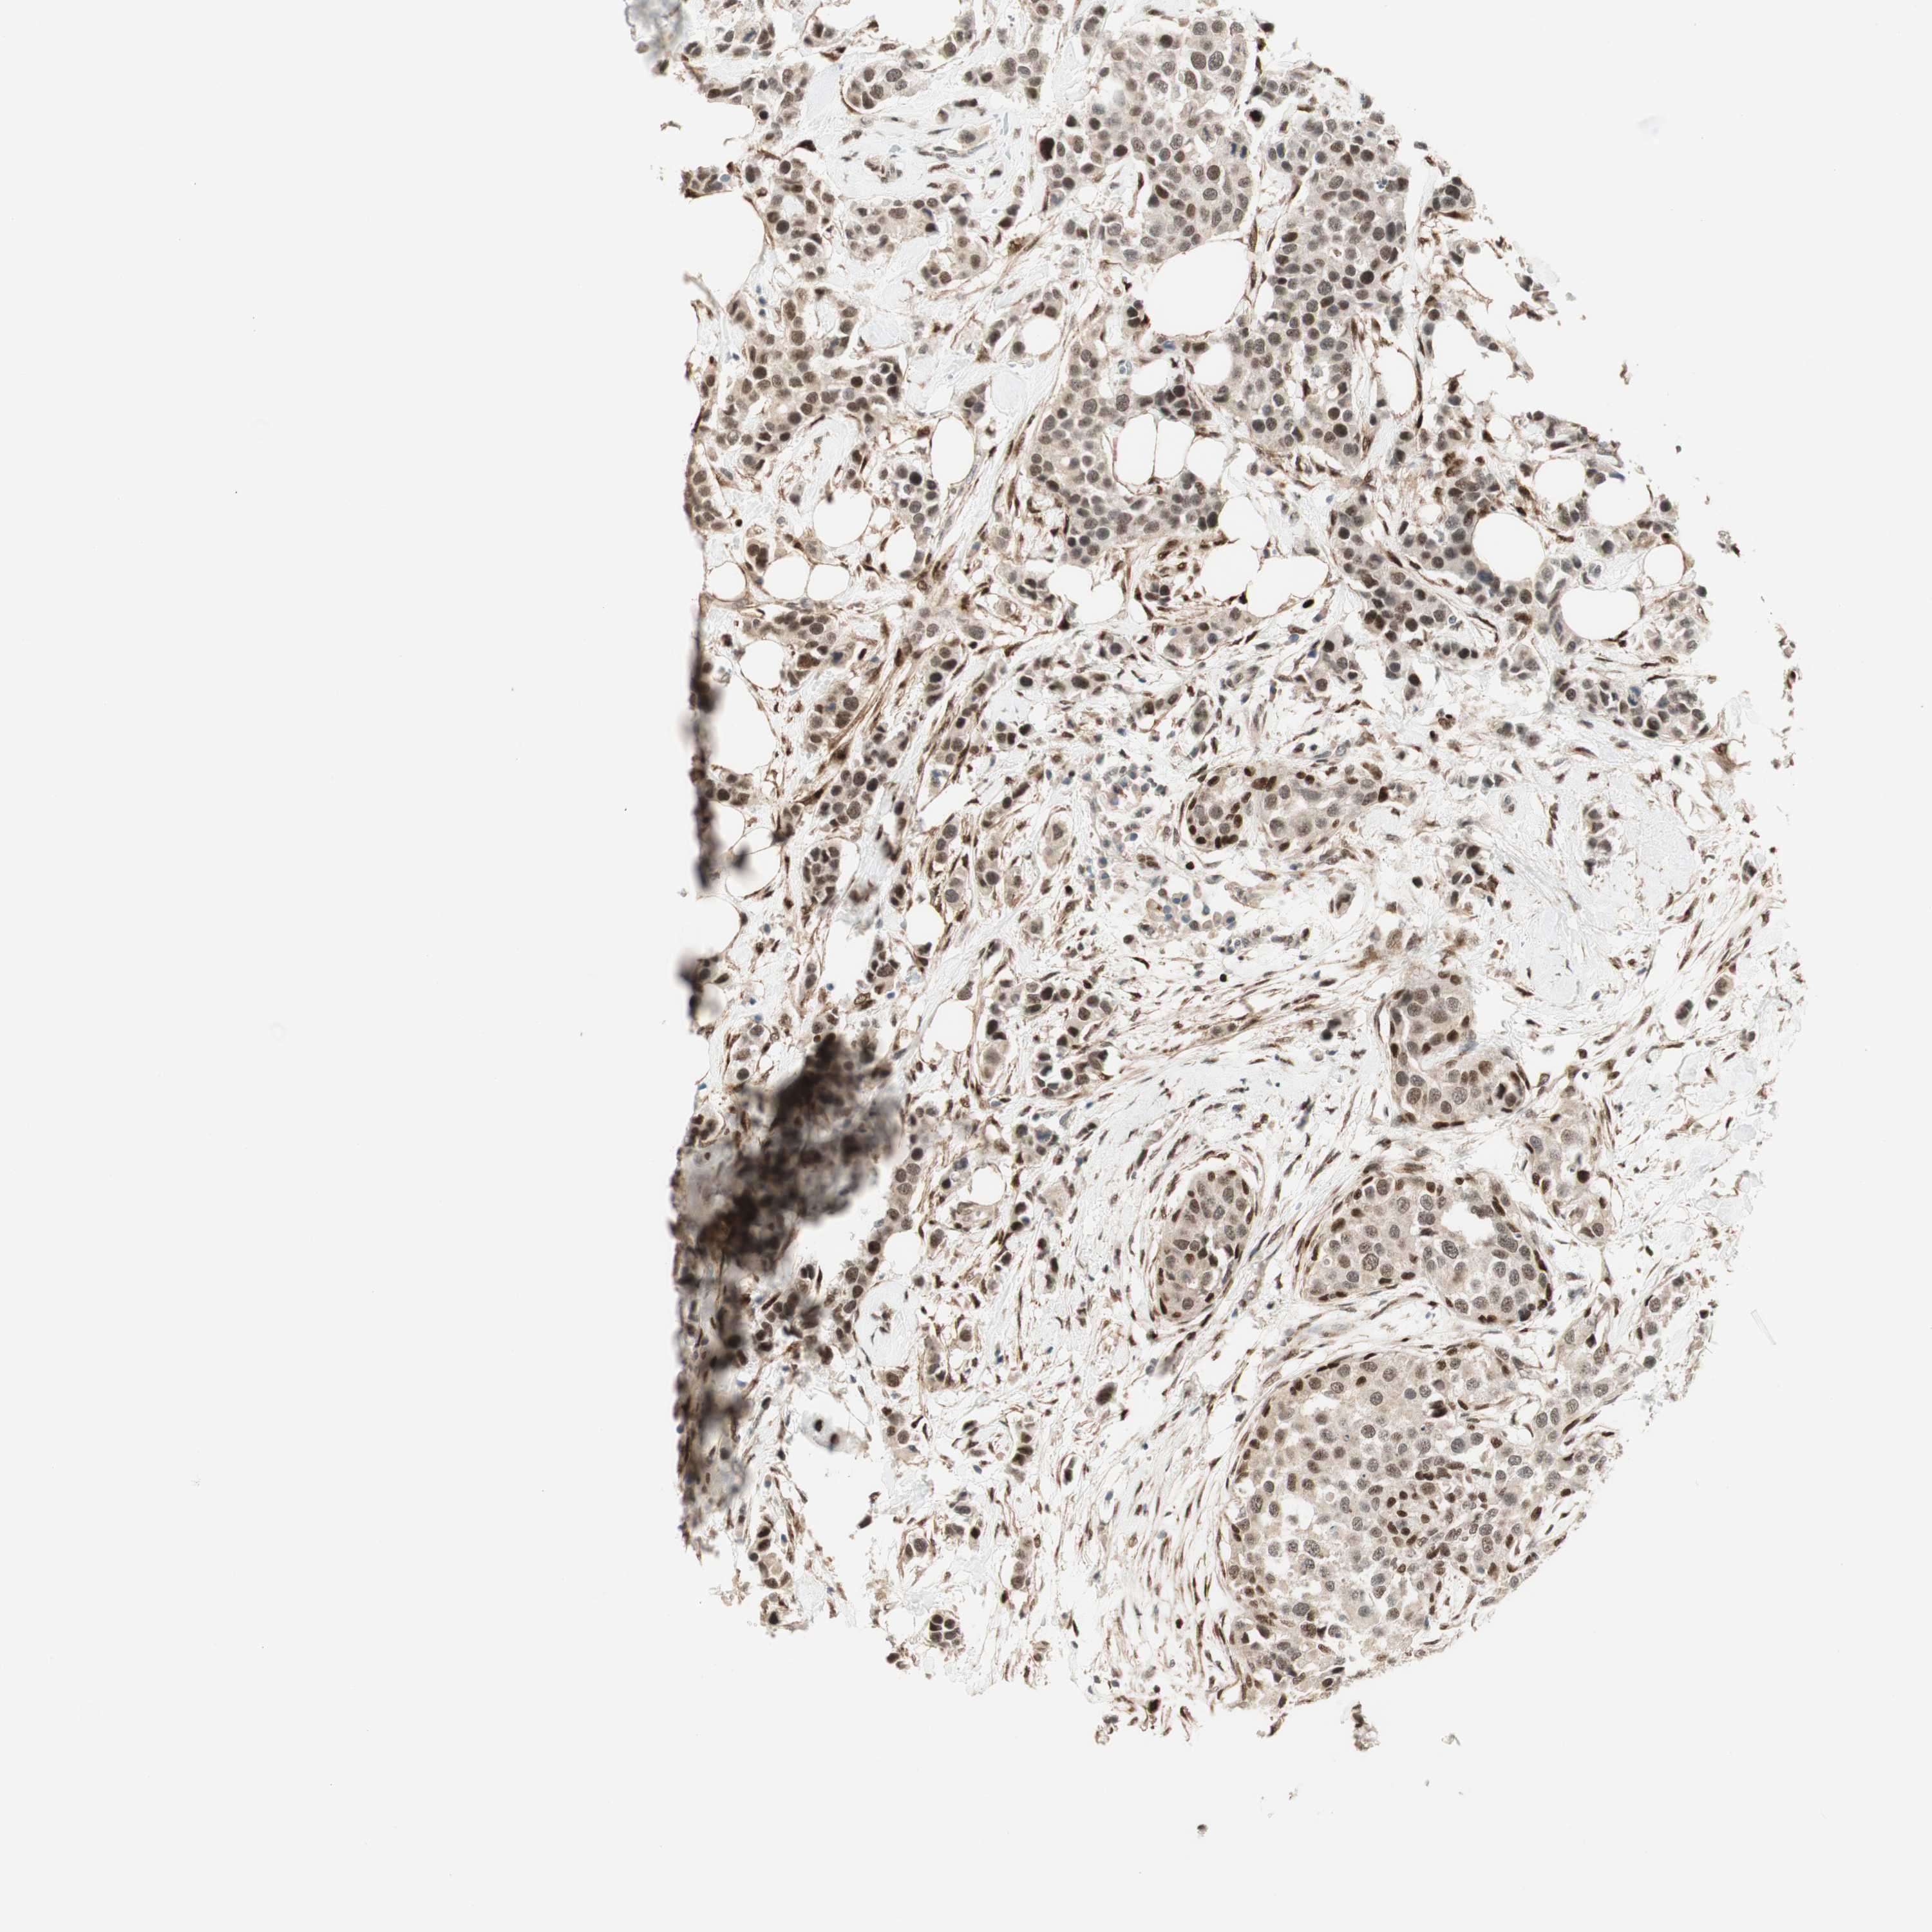

BRCA TCGA BRCA VALIDATION PROTEIN EXPRESSION

ANTIBODIES

AND

VALIDATION